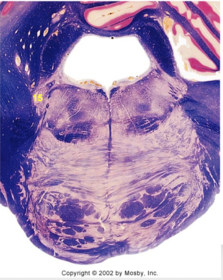

| Nucleus gracilis | |

| Accessory nucleus | |

| Medial longitudinal faciculus | |

| Pyramidal decussation | |

| Medullary pyramids | |

| Anterior spinocerebellar tract | |

| ALS | |

| Posterior spinocerebellar tract | |

| Spinal tract of V | |

| Spinal nucleus of V | |

| Nucleus cuneatus | |

| Fasciculus cuneatus | |

| Fasciculus gracilis | |

| Central canal | |